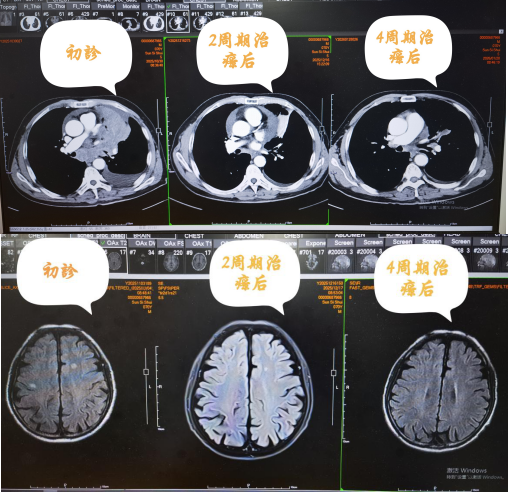

转入后,我们为患者行经皮穿刺肺活检术,结合胸部CT增强、颅脑MRI及免疫组化等检查,明确诊断为:左肺小细胞癌伴左肺门、纵隔淋巴结、脑转移(广泛期),病情危急。

2周期治疗后,患者全面复查评估疗效,结果显示:左肺肿瘤较前明显缩小,脑转移瘤较前明显缩小,疗效评估达到PR(部分缓解),随后继续行第3周期治疗。

至今,患者已顺利完成6周期化疗联合免疫治疗,期间无明显化疗后不良反应,整体状态良好,目前正在外院行颅脑放疗,进一步巩固治疗效果,争取更好的预后。